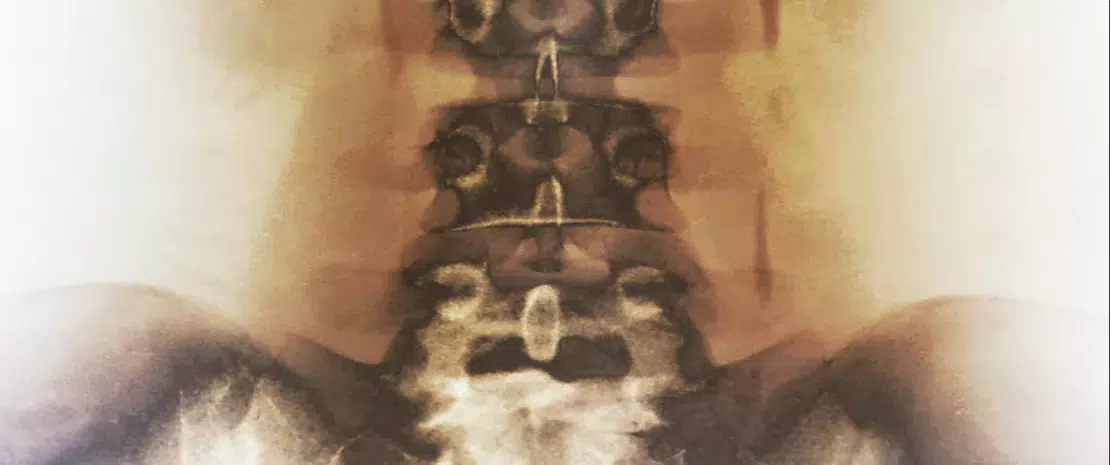

Une équipe italienne a étudié le microbiote intestinal de 52 patients ayant eu au moins deux épisodes symptomatiques de calculs rénaux constitués à plus de 80% de cristaux d’oxalate de calcium (groupe C+), et l’a comparé à celui de 48 témoins sains. Ce type de calcul est identifié dans 70 % des coliques néphrétiques, généralement sans cause primitive retrouvée. Seule l’alimentation (apports de calcium et d’oxalate trop importants) est actuellement incriminée dans la genèse de ces lithiases idiopathiques, souvent récidivantes. L’implication du microbiote intestinal avait déjà été suggérée par une étude mettant en évidence la capacité d’une bactérie intestinale (Oxalobacter formigenes)à dégrader l’oxalate, réduisant ainsi son absorption et son excrétion urinaire.

Ces nouveaux travaux étayent l’hypothèse : les échantillons du groupe C+ comprenaient une diversité plus faible et sur le plan taxonomique une représentation significativement inférieure de trois genres : Faecalibacterium, Enterobacter, Dorea. En revanche, la proportion d’Oxalobacter formigenes détectée dans chaque échantillon était très faible, et sans différence entre les groupes. Les scientifiques ont ensuite recherché une éventuelle différence d’activité de dégradation oxalique. Cinq échantillons de chaque groupe ont été testés par une méthode de séquençage spécifique ciblant les gènes impliqués dans la dégradation de l’oxalate. Les échantillons du groupe C+ contenaient une proportion réduite de ces gènes inversement corrélée à l’oxaliurie des 24h et à son excrétion dans les selles. Cette approche génétique a également permis d’identifier pour la première fois des bactéries et des archées porteuses de gènes impliqués dans la dégradation de l’oxalate (Escherichia coli entre autres) qui étaient plus représentées dans le groupe de témoins sains.